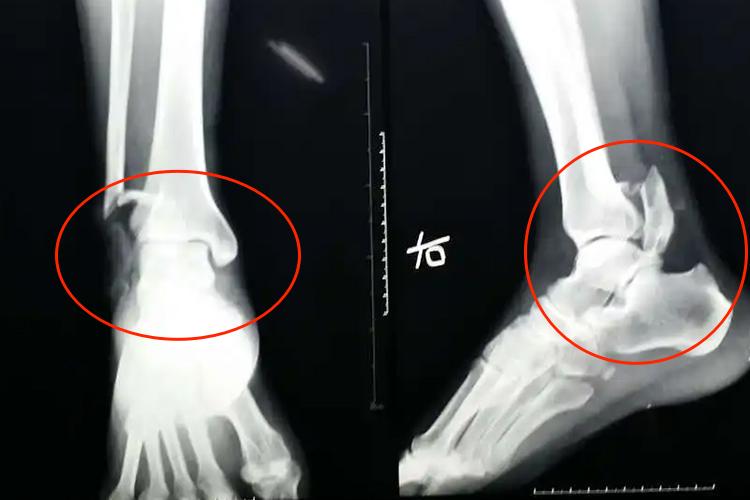

粉碎性骨折是临床上用于描述骨折的名词,其X线检查可见在骨折部位有三块以上碎裂的骨质,骨折线呈T形或Y形。同时,粉碎性骨折患者的患处可合并有明显的疼痛、肿胀,也可出现张力性水疱和皮下瘀斑,还可伴有患肢活动受限。